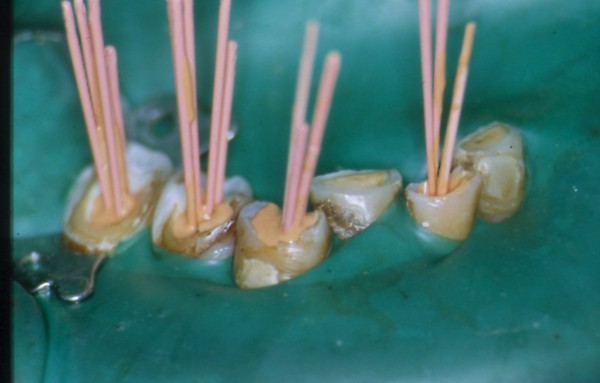

INTRODUCCIÓN El Bruxismo como entidad somática asociada al stress, responde a la mecánica de un Círculo Vicioso Patogénico, que Kawamura describiera hace ya muchos años. FACTOR DESENCADENANTE , que proveen las Interferencias a nivel dentario. En las entregas anteriores se desarrollaron las bases conceptuales de una OCLUSIÓN ORGÁNICA y los efectos de una mayor o menor Desoclusión según la variabilidad de los diferentes Factores Determinantes de la Oclusión. En síntesis; A-La obtención de una Oclusión en Relación Céntrica, nos permite devolver al sistema una elongación muscular fisiológica, sin acortamientos ni estiramientos musculares, sin las consecuentes estimulaciones de los husos neuro musculares, y; una situación estable de la A.T.M. con espacios articulares uniformes. B-El logro de una Guía Anterior que permita desocluir los sectores posteriores durante los movimientos excursivos, nos provée de una segunda y preponderante senda a transitar, que NO estimula por sus contactos excursivos la cincha Pterigo Maseterina, causante de las enormes destrucciones parafuncionales que es frecuente ver en bocas bruxómanas, y la axialización de las fuerzas sobre las piezas posteriores durante el cierre. C-Otorgando como consecuencia, Estabilidad a la tabla premolar-molar, simultaneidad en la recepción de fuerzas durante el cierre(A.T.M. y superficies oclusales). Obtendremos así una Oclusión estable y fisiológica, que no genere el FACTOR DESENCADENANTE del Bruxismo, siempre presente a nivel dentario. INTRODUCTION Bruxism as a somatic entity associated with stress responds to the mechanics of a Pathogenic Vicious Circle, described by Kawamura many years ago. Summarsing: A-Obtaining an oclusion in a Central Relation, allows us to return to the sistem a physiological muscular elongation, without muscular shotthenings or lenghthenings, without the following stimulations of the neuro-muscular huses and a stable situation of the Temporo Mandibular Joint with uniform articular spaces. B-The accomplishment of an Anterior Wide wich may allow disclusive the posterior sectors during the excursives movements, and the axial forces during the mandibular closure. C-Providing as a consecuence, axiality and stability to the posterior sections, responsible of the mandibular closure, through Sttopers, Equalitzers, A, B and C, to obtain a Oclusión Mutuamente Compartida: forces reception during mandibular closure (T.M.J. and Oclusal Surfaces) By this procedure, we should obtain a stable and physiological oclusion, that will not generate the chain link of factors that lead to Bruxism, always present at the dental level. MATERIALES Y MÉTODOS: La funciones articular y muscular, se analizaron mediante Bio Pack, en el pre, en el intra y en el post operatorio. Durante el diagnóstico, tratamiento y remontas, se utilizaron articuladores semi ajustables Wip Mix, totalmente ajustables Artex y arcos faciales correspondientes. El encerado de dianóstico se realizó, mediante la técnica de encerado progresivo de Peter K. Thomas. Los refuerzos a Perno Colado se llevaron a cabo con oro BIODENT YELLOW de ARGEDEN. Los tres juegos de provisionales utilizados, se hicieron con metacrilato termo curado. Las Restauraciones Periféricas Totales, fueron realizadas mediante porcelana CREATION de WILLY GUÉLLER, sobre oro BIODEN YELLOW de ARGEDEN. Los chequeos de los Contactos Interoclusales, se midieron con papeles de articular de 40 y 12 micrones, y mediante el analizador computarizado T-Scan. DESARROLLO Paciente varón de raza blanca, 42 años, complexión robusta y marcada hipertrofia maseterina. Fig.1 Fig.2 Fig.5 Se realiza un análisis pre-operatorio articular y muscular mediante Bio Pack, y oclusal mediante T-Scan, cuyos resultados muestran una evidente hiperactividad muscular en Temporal Anterior y Masetero Derechos, y contactos totalmente anómalos tanto en Oclusión Habitual como en Excéntricas. Fig. 6-7-8-9-10-11 Sensor de ruidos articulares Luego del primer intento de relajación mediante Laminillas de Long (Ref.6),Fig.12, registros y montaje, se observa la aparente presencia de una relación Borde a Borde, que luego se comprobaría que se trataba de una propulsión exagerada de su mandíbula en la búsqueda de contactos efectivos. Fig. 13-14 (Obsérvese el fenómeno de Patterson dado por la exclusiva guía de movimiento de la A.T.M. y la carencia de la Guía Anterior) Se procede a construir un JIG de LUCIA para lograr una desprogramación muscular adecuada, y se le indica permanecer con el colocado durante toda la noche anterior a la consulta, sin contactos dentarios posteriores. Aún en la duda, de que la obtenida sea una posición articular fisiológica, se procede a construir una Placa de Relajación sobre el último montaje obtenido, la que se ajusta cada dos días, y al cabo de tres semanas se procede a un tercer montaje obtenido de la nueva situación posicional. Fig.17-18 Se verifica entonces que estamos en realidad, ante una presunta CLASE II, después de tres métodos diferentes de relajación y transcurridos más de un més de múltiples sesiones para lograr una posición diagnóstica confiable a partir de donde comenzar a trabajar.(O.R.C.) Se adicionan entonces topes (montículos) en las caras oclusales de los primeros molares de la Placa de relajación, transformándola en una Férula Pivotante, de levísima altura, impidiendo el contacto de las demás piezas dentarias a fin de convertir la palanca en una de clase II (fisiológicamente el sistema se mueve según una palanca de clase III), y obtener de esa forma una descompresión de los espacios articulares, ya que si bien la A.T.M. era asintomática, estaba muy claro que la Dimensión Vertical Posterior se presentaba disminuida debido al exagerado desgaste de todos los sectores posteriores, cuya típica forma de «desgaste en olla», se verificaba en el análisis estático de los modelos.( Ref.7) En esa situación se remonta el modelo inferior puesto que el superior no modifica su posición espacial, y se realiza un Encerado de Progresivo Diagnóstico según PKT, previo análisis de los modelos mediante los analizadores de W.McHorris (Ref.8) Fig.18-19-20-21-22-23-24-25-26-27-28-29-30 Fig.18 Fig.22 Fig.23 (Obsérvese, que la Disclusión Propulsiva comienza en los rebordes mesiales del canino, sigue en los rebordes distales del lateral, y finaliza con los rebordes mesiales de los centrales.) Se realizan las endodoncias de toda la boca y se tallan los endodontos para la construcción de Pernos Muñones Colados de oro, los que se realizarán mediante técnica indirecta sobre los modelos :montados según los logros de todos los procedimientos de relajación. Se torna imprescindible la extracción de tres piezas dentarias, para la confección de la Guía Anterior, cuyo alineamiento hubiera sido imposible mediante técnicas reconstructivas ya que la posibilidad ortodóntica no era viable dadas las condiciones de desgaste. Fig.31-32-33-34-35-36-37 (Obsérvese, que desde la configuración de los Pernos Muñones Colados, se determina ya la Alineación Tridimensional que otorgaremos a la Rehabilitación Oral Integral del caso. Se monta entonces el primer juego de Provisionales de acrílico de termo curado, obtenido de la réplica del Encerado de Diagnóstico. Fig.38-39-40-41 (Obsérvese la presencia del ajuste periférico y las disclusiones, tan importantes en las provisorias como en las definitivas ya que del resultado de la etapa de provisionales, dependerá el éxito final.) Se ajustan las Unidades de Oclusión mediante Ajuste Oclusal (según técnica propuesta por la Cátedra de Operatoria Dental II y Prótesis de la Fac. de Odontología, Univ. Bs. As., Prof.Anibal Alonso.) Se deja actuando la nueva situación durante seis meses. Han transcurrido seis meses durante los cuales se instaló un nuevo juego de provisorios con las mismas características del anterior, y clinicamente no se observa hiperactividad muscular, perforaciones de los provisorios, molestias para desmenuzar los alimentos ni síntomas alguno en la A.T.M. NOS ENCONTRAMOS, CON UN SISTEMA EN PAZ A TODOS SUS NIVELES. Se procede entonces a la toma de impresiones definitivas, mediante la técnica de Impresión a Presión Masticatoria, para la confección de las restauraciones permanentes, y los metales se chequean mediante llaves de Duralay, para observar la situación análoga entre laboratorio y clínica.(Corroboración de la Oclusión en Relación Céntrica)Fig.42-43-44 Se prueban los metales y verifica su ajuste periférico. (Obsérvese que también en los metales sub porcelana se siguen las formas de las Preparaciones Funcionales, permitiendo de esta manera un perfecto bizcochado de la porcelana supra metal.) Realizada la Guía Anterior, Determinante Oclusal Primario y Anterior en el laboratorio, se prueban en boca sus características estáticas: Altura Funcional, Ángulo de la Disclusión y Punto de Acoplamiento, como así las dinámicas: Laterotrusión Derecha e Izquierda y Propulsión. En este estado las cosas, tenemos al sistema circunscripto tanto estática, como dinámicamente, por el gobierno de dos comandos, ya en Oclusión en Relación Céntrica, como en las Transtrusiones: Sabemos que todo lo que construyamos (tabla premolar-molar), entre estos dos comandos rectores del movimiento, partirán del mismo punto y volverán a el, transitando el recorrido impuesto por los mismos. Se construyen entonces en el laboratorio, las unidades de oclusión de premolares y molares, siendo las correspondientes a los cuatro últimos molares, con oclusal en oro, como un elemento de detención del cierre más poderoso que la porcelana.47-48-49-50-51 Se prueban en boca la Curva de Wilson, la Curva de Spee, la Alineación Tridimensional, los Espacios Uniformes Disclusivos, la Dirección de los Surcos de T, nT, y P, y los Puntos Interoclusales de Contacto. En laboratorio se retocan entonces los Puntos Interoclusales de contacto, acercando los mismo a la mejor posición ideal lograble, y luego de una nueva prueba en boca, se glacéan las piezas y se instalan en forma provisional durante 24 hs. Verificada la eficacia de las formas (FORMA=FUNCIÓN), se procede a constatar la eficiencia de la dinámica trayectorial y se cementan con cemento de fosfato mediante la técnica de cementado alterno. Fig.54-55-56-57-58-59-60-61-62-63-64-65-66-67-68-69. Fig.54 Fig.55 Curva de Wilson y Alineación Tridimensional en molares y premolares sup. Der. Fig.56 Fig.57 idem inferiores derechos Fig.58 Fig.59 Idem superiores izquierdos CONTACTOS INTEROCLUSALES SUPERIORES CONTACTOS INTEROCLUSALES INFERIORES Transcurrido un mes de instalada la Rehabilitación, se lleva a cabo un nuevo estudio, post operatorio con Bio Pack y Tscan. CONCLUSIONES : I-El paciente realiza una apertura bucal de 45mm sin forzamientos siguiendo una misma línea de apertura sin desvíos. II-Las disclusiones en laterotrusión se llevan a cabo mediante un recorrido lineal sobre los rebordes medios de ambos caninos superiores, creando un fenómeno de Luce con espacios uniformes en ambos lados. III-La disclusión en propulsión se manifiesta comenzando en los rebordes mesiales de ambos caninos, siguiendo por los rebordes distales de laterales y terminando en los rebordes mesiales de ambos centrales, dando lugar a un fenómeno de Christensen con espacios uniformes de ambos lados. IV-Los contactos interoclusales son suficientes, simultáneos y tripódicos logrando la estabilidad en ambos planos del espacio tanto de las piezas individuales como en conjunto, sin contactos deflectivos. V-Realizado un nuevo montaje de la boca terminada, corroboramos como estable la Oclusión en Relación Céntrica. VI-No existen movilidades dentarias y los tejidos periodontales y gingivales se encuentran estabilizados. VII-No existen ruidos articulares. VIII-El resultado post operatorio Bio Pack de la dinámica mandibular, muestra una sustancial mejora de los movimientos en los tres planos del espacio. IX-Electromiográficamente, se observan contracciones musculares dentro de los rangos de normalidad, persistiendo un rango ligeramente elevado en temporal anterior y masetero del lado derecho, presumiblemente debido a la hipertrofia que dicho paciente traía, y mostraba en el estudio pre-operatorio. COMPARACIONES PRE, INTRA Y POST OPERATORIAS Sonografía de la ATM: Tanto en el examen pre como post operatorio no se observaron ruidos de ningún tipo, coincidiendo con la exploración clínica pre auricular e intra auricular. Electromiografía: La electromiografía en reposo, muestra bien a las claras la presencia de músculos hipertónicos durante el estudio pre operatorio, fundamentalmente del grupo Temporal Anterior y Digástricos, estando el Masetero izquierdo ligeramente por encima de su rango normal como así también ambos Esternocleidomastoideos. Durante el estudio post operatorio, se verifica el estado tónico de todos los grupos musculares, persistiendo una ligera hipertonicidad de rango levemente por encima de lo fisiológico, en el Temporal Anterior Derecho y Digástrico Derecho. PRE OPERATORIO POST OPERATORIO Temporal Ant. Der. 4.4 2.8 Temporal Ant. Izq. 6.2 1.1 Masetero Der. 1.2 0.5 Masetero Izq. 1.5 0.8 Est.Cleid.Mast. Der. 1.6 0.3 Est.Cleid.Mast. Izq. 2.1 0.2 Digástrico Der. 1.7 2.9 Digástrico Izq. 1.6 0.7 (La unidad de medida utilizada es el microvoltio ) Dinámica mandibular: Durante el Pre Operatorio, en el Plano Sagital, tanto la Apertura como el Cierre lento, se manifiesta mediante una acentuada tendencia a propulsar la mandibula. Durante el Post Operatorio, la tendencia hacia la derecha de estos dos últimos planos se mantiene, mientras que en Plano Sagital, la propulsión inicial no se produce, asemejándose el movimiento a la primera fase del Bicuspóide de Posselt. El Análisis de la Dinámica realizado durante la Masticación (chicle), nos muestra en el Plano Sagital, la propulsión mencionada durante la apertura y cierre lentos durante el estudio Pre Operatorio, se aproxima a la normalidad durante el Intra Operatorio (2º juego de provisionales), y se vuelve a manifestar propulsivo, en el Post Operatorio. En cuanto al Plano Frontal, durante el Pre Op. , ofrece un Ciclo Masticatorio(recordar la forma de «gota de agua») para el lado izq., con componentes derechos e izquierdos alternos, que se aproximan paulatinamente al Ciclo Masticatorio Normal, durante el Intra y Post Operatorio. El Plano horizontal, confirma las afirmaciones anteriores durante los tres períodos de estudio. ANÁLISIS MEDIANTE TSCAN 1-Bio Pack Bio Research Associates,Inc Distrib.UEDA S.A. 2-Wip Mix-Artex 3-Au:89% / Pt:6% /Elementos complementarios:5% 4-Idem ref.3 5-Tscan TekSkan,Inc Distrib.UEDA S.A. 6-Mc Horris.Cátedra de Operatoria Dental II y Prótesis. 7-Alonso.Cátedra de Operatoria Dental II y prótesis. 8-Mc.Horris. Analizadores de Guía Anterior. BIBLIOGRAFÍA: 1-Esquemas de las dos primeras entregas, tomadas del libro:»Oclusión Orgánica…un camino hacia la Rehabilitación Oral» 2-Oclusión y Diagnóstico en Rehabilitación Oral. 3-Anatomia Odontológica. 4-A contribution to the study of the movementes of the mandible. 5-Celenza F.W, Nadeskin J.F.,Oclusión.Situación actual. 6-D´Amico 7-Dawson P.E. 8-Huffman -Regenos. 9-Hobo S.-Takayama H.A. 10-Lucia V.O 11-Mc Horris. 12-Mc Horris. 13-Posselt U. 14-Stuart C. 15-Vartan Veshnilian AGRADECIMIENTOS: La Rehabilitación Oral, especialidad donde se hace imprescindible el manejo y concurrencia de todas las especialidades dentales en su desarrollo más depurado, no tendría razón de ser, sin la más estrecha colaboración de una técnica para- médica con detalles de excelencia. Sr. Pedro Colomina: muchas gracias. Pedro Colomina. – Titulado especialista en prótesis dental en la escuela Ramon y Cajal de Barcelona 1988

A la inspección se observan Facetas Parafuncionales Terminales (tipo 2 y 3 con compromiso pulpar), con un 75/90 % de reducción morfológica en la mayoría de las piezas dentarias.

La Guía Anterior es inexistente y el desgaste premolar-molar nos habla de una pérdida de Dimensión Vertical , tanto anterior como posterior.Fig.1-2-3-4-5

Los tallados se han realizado bajo el concepto de Preparaciones Funcionales Gnatológicas.)